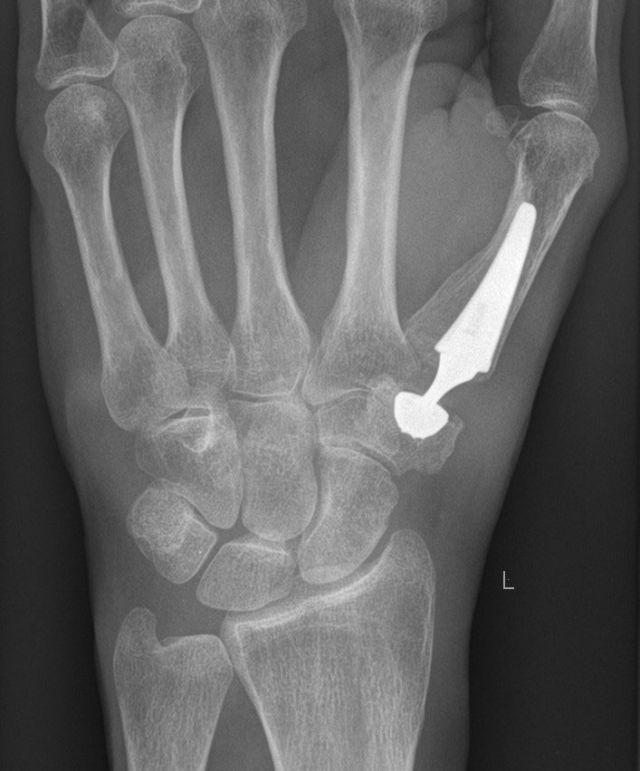

Seit Anfang 2019 führen wir auch wieder die Implatantation von Kunstgelenken (Gelenkprothesen) in das Daumensattelgelenk durch. Es gibt Sattelgelenksprothesen bereits seit über 3 Jahrzehnten, allerdings zeigten diese keine guten Langzeitergebnisse. Seit kurzem sind jetzt Prothesen auf dem Markt, welche die konstruktiven Probleme der "alten" Systeme beseitigt haben und deutlich bessere Langzeitergebnisse versprechen.

Im Vergleich zur RSA hat die Sattelgelenksprothese den Vorteil, dass das grosse Vieleckbein erhalten bleibt und bei einem eventuellen Versagen der Prothese die RSA weiterhin möglich wäre.

Die Prothese hat auch den Vorteil einer kürzeren Nachbehandlungszeit von durchschnittlich 8 Wochen, allerdings ist der technische Aufwand der Operation deutlich höher als bei der RSA.

Postoperatives Röntgen: Implantierte Daumensattelgelenksprothese